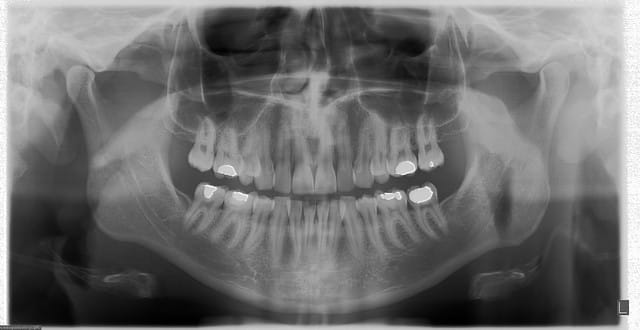

très belle définition

Les radios sont extraordinaires !!!! Quel beau jouet ,ça fait envie.

instrumentarium

mieux que chez le radiologue...

et pour moi ca semble être le TOP

D'accord avec Marc: la pano est magnifique !

panos pr les nouveaux patients qui presentent pas mal de caries ou de prothèses en bouche APRES la 1ère C, bilan odf, pano pr les gamins en cours de traitement odf une fois par an(surveillance), ATM pr ts les SADDAM diagnostiqués, pano en vue implants pr savoir si on pousse jusqu'au scan , c'est trop pr toi?